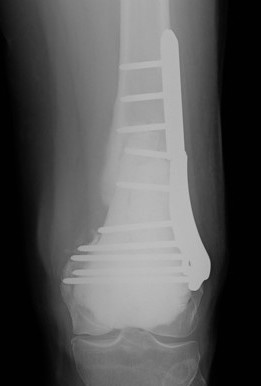

Wide resection and Allograft / Prosthesis Reconstruction

Indications

- extensive soft tissue tumour

- extensive cortical destruction

- impossible joint salvage

- multiple recurrence / failure bone cement